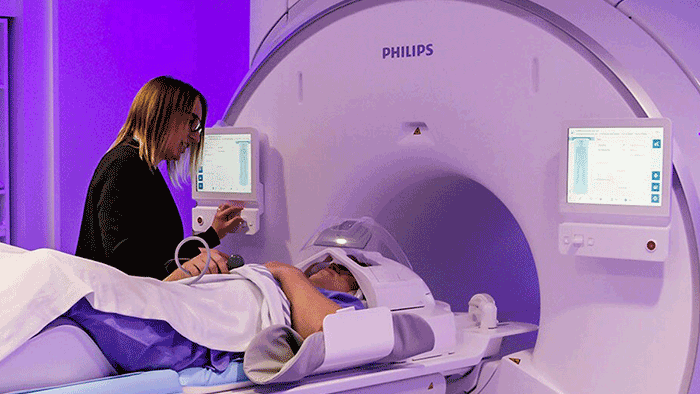

University Hospital Münster (UKM) radiologists and researchers are among the world’s first to experience what the high gradient power of MR 7700 means for clinical research studies. The team is eagerly exploring the 3.0 Tesla MR system’s potential for supporting their ongoing neuroscience research and innovations in prostate, liver and lymph node imaging. For diffusion imaging in particular, they see markedly higher SNR, shorter scan times and reduced distortions.

At UKM, the team led by Dr. Walter Heindel operates six MRI scanners. Their latest addition, the Philips MR 7700 is dedicated to research and was chosen for the strength and quality of its XP gradients and numerous other innovations.

In its first few weeks of operation, more than 100 patients and volunteers have been scanned on the MR 7700. Initial projects for which the team will harness the system include high-resolution multiparametric prostate MRI, developing innovative protocols for stroke imaging, and diffusion studies of the lymph nodes.

Easy design of imaging protocols and amazing patient comfort

Dr. Heindel has received impressions that MR 7700 operation has been straightforward. “My highly specialized team of MR physicists raves about the ease of use of the system, especially the simple implementation of new imaging protocols. The low effort required to modify scan parameters and protocols enables fast and easy experimentation with imaging techniques,” he says. “This clearly distinguishes Philips and was one of the reasons to choose this system.”

There has also been positive feedback from patients. “One patient told me that she had never had an MRI examination that was so comfortable,” Dr. Heindel says. “By virtue of the softness of the ComfortPlus mattress, combined with the short exam time, she was surprised at how pleasant the experience was, while in earlier examinations at other sites she just wanted to get out of the system. She said she would definitely drive the long distance again to have her follow-up examination also in this system.”